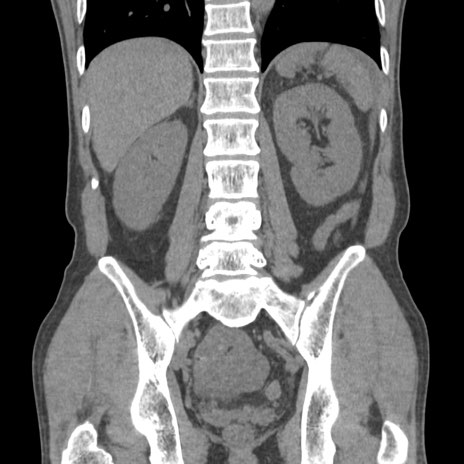

症例56 CT(冠状断像)

脂肪ウインドウ